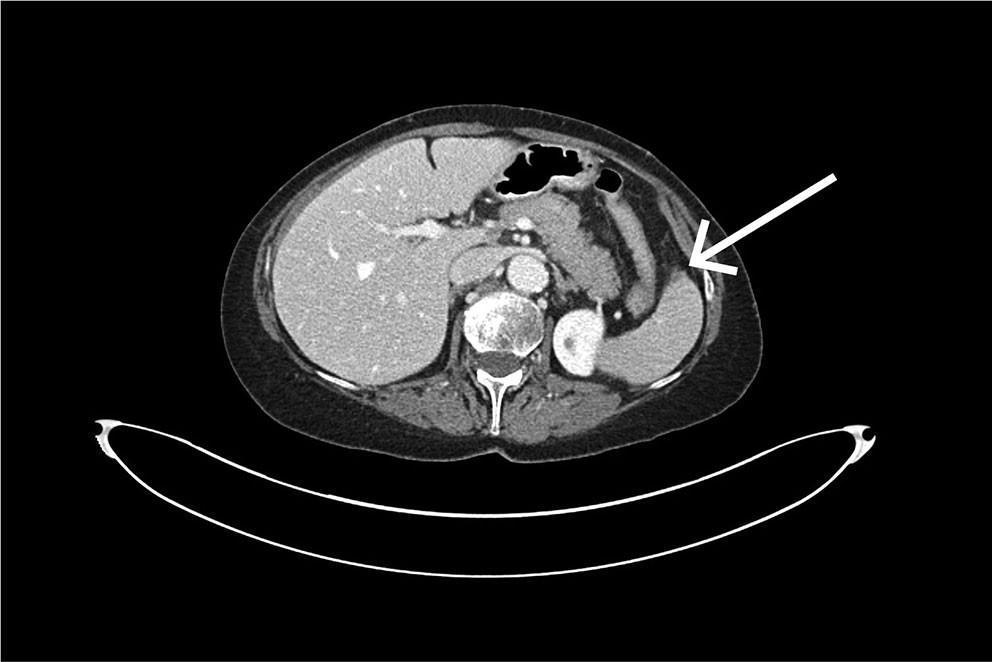

An urgent CT scan of the abdomen and pelvis with intravenous contrast in the portal venous phase was performed. The examination revealed a large subcapsular splenic haematoma and a small splenic laceration (Figure 1). It was concluded that a capsular rupture had likely occurred, with bleeding into the free abdominal cavity and fluid accumulation around the liver, colon and pelvis. Upon re-examination of the CT scan taken immediately after the colonoscopy, a small subcapsular splenic laceration was visible near the attachment of the splenocolic ligament (Figure 2).